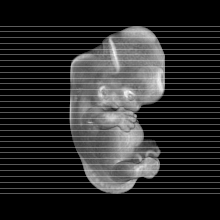

Carnegie Stage 20 (50 post-ovulatory days)

Most embryos at stage 20 are approximately 50-51 postovulatory days old and measure 21-23 mm in length. Distinguishing criteria for this stage include upper limbs slightly bent at the elbows, short stubby fingers, hands curving over the cardiac region but still far apart from each other, and a fringe-like vascular plexus that marks growth centers laterally in the superficial tissues of the head.